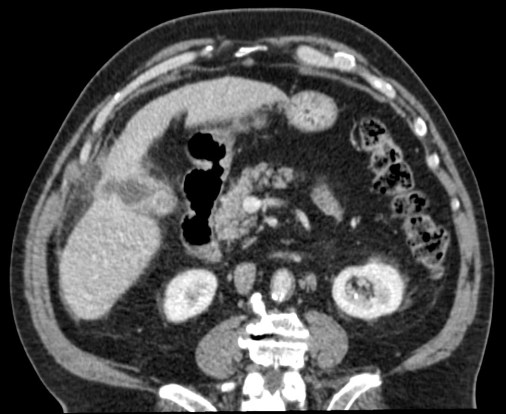

Se realizó posteriormente TC abdominal por mala evolución del paciente:

– La TC se reserva para pacientes con dudas diagnósticas o con discrepancia clínico ecográfica. Se obervarán los mismos hallazgos que en la ecografía, además del aumento de densidad de la pared de la vesícula, del parénquima hepático o especialmente la presencia de otras complicaciones.

- Colecistitis xantunogranulomatosa: nódulos o bandas intramurales. Se producen por la oclusión de los senos de Rokitansky Aschoff de la pared, los cuales se rompen, luego la bilis coloniza la pared y finalmente produce una reacción inflamatoria a la que puede sobreañadirse una infección. Es un factor de riesgo para el carcinoma.

- Eco y TC: Litiasis + engrosamiento mural focal o difuso. Puede haber cambios inflamatorios pericolecísiticos. Los nódulos hipocogénicos o bandas pueden sugerir el diagnóstico específico de c. xantunogranulomatosa.

- El diagnóstico raramente se realiza previo a la cirugía y al análisis histopatologíco.